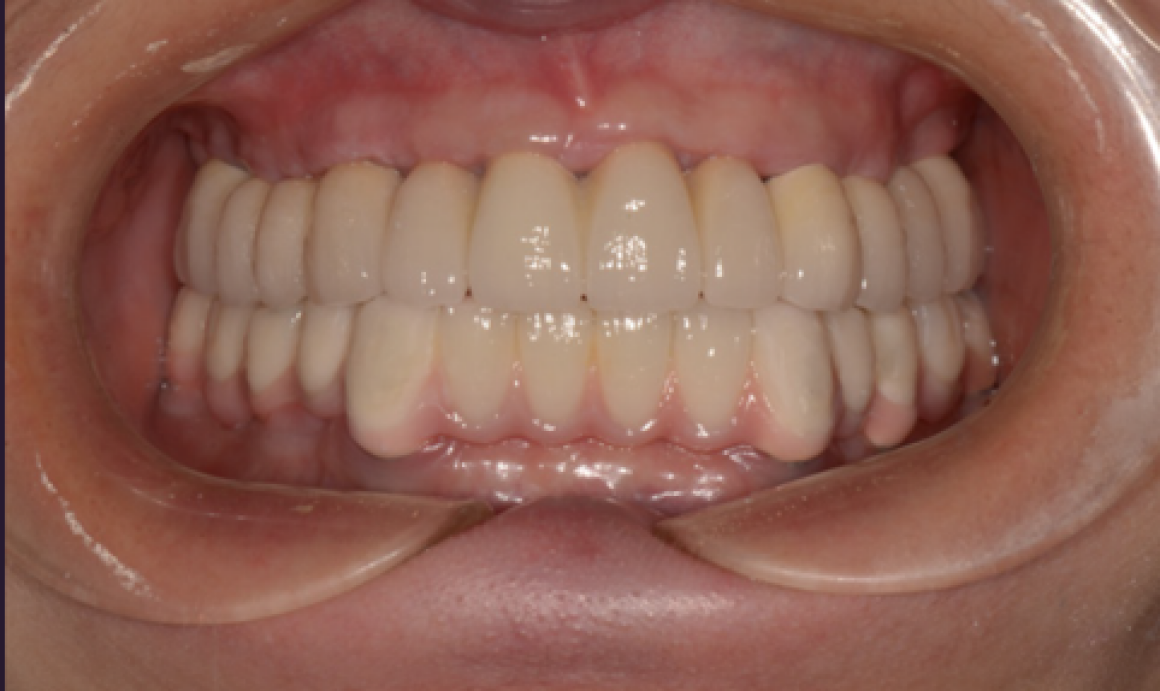

Тотальная реабилитация

Проблема: Отсутствие зубов